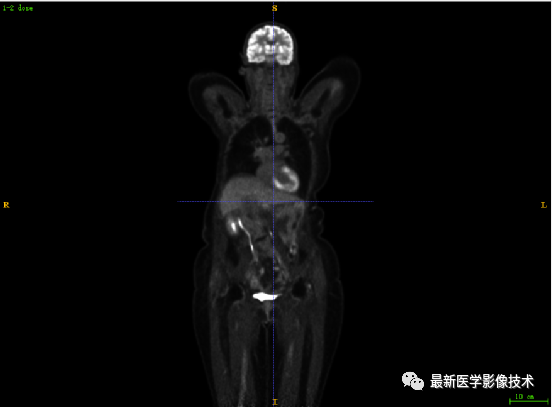

7.1、低剂量2重建结果

第一张是低剂量2的PET图像,第二张是full剂量PET图像,第三张是网络重建的PET图像。